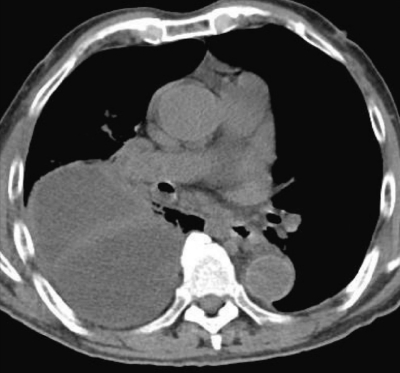

検査所見:血液所見:赤血球 355 万、Hb 12.1 g/dL、Ht 36 %、白血球 16,500 (桿状核好中球 25 %、分葉核好中球 65 %、好酸球 1%、単球 2%、リンパ球 7%)、血小板 40 万。血液生化学所見:総蛋白 5.9 g/dL、アルブミン 2.2 g/dL、AST 29 U/L、ALT 18 U/L、LD 173 U/L(基準 176〜353)、ALP 223 U/L(基準 115〜359)、γ-GTP 44 U/L(基準 8〜50)、CK 260 U/L(基準 30〜140)、尿素窒素 35 mg/dL、クレアチニン 1.6 mg/dL、血糖 161 mg/dL、HbA1c 5.7 % (基準 4.6〜6.2)、Na 131 mEq/L、K 4.3 mEq/L、Cl 97 mEq/L、Ca 8.4 mg/dL。CRP 31 mg/dL。動脈血ガス分析(room air):pH 7.55、PaCO2 32 Torr、PaO2 56 Torr、HCO3- 28 mEq/L。心電図で異常を認めない。臥位のポータブル胸部エックス線写真と胸部CTとを別に示す。

この画像所見をきたす原因として最も考えられるのはどれか。

次に行うべき検査はどれか。